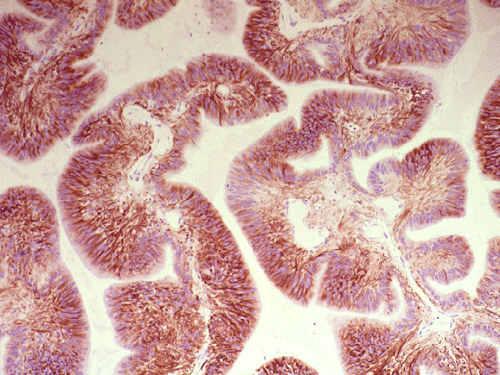

On immunohistochemistry, the luminal boder of the cells are strongly positive for epithelial membrane antigen (EMA) (Panel D). The tumor cells are also strongly positive for glial fibrillary acidic protien (GFAP) (Panel E).

On immunohistochemistry, ependymomas usually demonstrate widespread positivity for glial fibrillary acidic protein (GFAP). The tumor cells, particularly the luminal surface of ependymal canals or papillary ependymoma are positive for epithelial membrane antigen. Over 80% of ependymomas are positive for CD99 4, 5. However, a small number of other neuroepithelial tumors are also positivie for CD99, this feature is not a full proof diagnostic help. For low-grade ependymomas the progression free survival time is significantly shorter with Ki-S1 labeling index over 5%, and for tenascin, VEGF, and EGFR positivity on immunohistochemistry. For high-grade ependymomas PFS was found to be significantly reduced for age under 16 years, subtotal tumor removal, p27 labeling index under 20%, p53 positivity, and for apoptotic index under 1% 6. Decreased expression of p14ARF protein expression is also related to aggressive biological behavior 7.